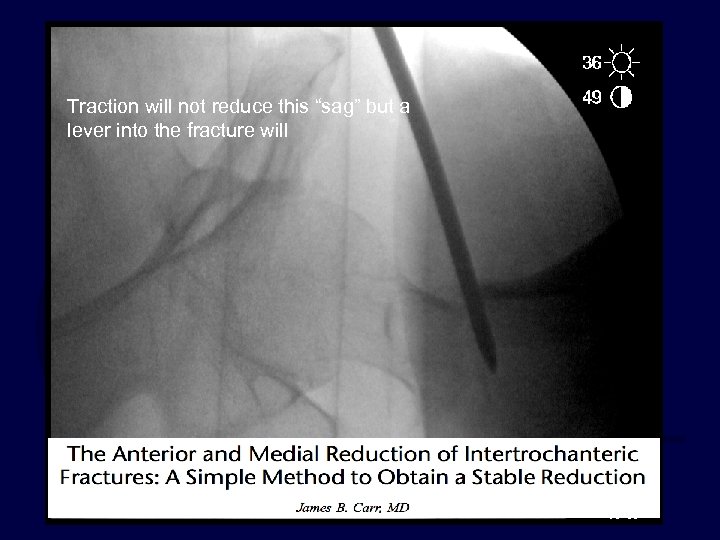

Traction will not reduce this “sag” but a lever into the fracture will

Traction will not reduce this “sag” but a lever into the fracture will reduce it